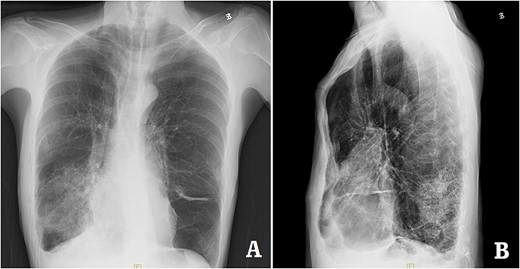

The patient was a 29-year-old male. He was found to have protrusive deformity on the anterior chest wall since childhood. The deformity was not serious in early years, but worsened after adolescence, with the lower part of the sternum protruding at an acute angle. At the age of 25, he developed right spontaneous pneumothorax and received surgical treatment at local hospital, but his thoracic deformity was not treated. As the deformity continued to worsen, which seriously affected the appearance of the chest wall, the patient was admitted to our hospital for surgery. Preoperative physical examination showed that the anterior chest wall was protrusive seriously, with a sharp tip protruding forward. The rib arches on both sides were slightly depressed (Fig. 1). Imaging examination showed that the anterior chest wall was protrusive, and the lower end of the sternum was at the forefront of the protrusion. His heart moved to the right, and the rib arches were slightly depressed (Figs 2–4). The operation was performed under general anesthesia. Two longitudinal incisions were made on both sides of the chest wall respectively. The incisions were located between the front axillary line and the median axillary line, with the length of ~5 cm. The chest wall muscles were dissected to expose the ribs in the incisions. Two tunnels were made on the highest plane of the protrusion, with interval of 3 cm. The tunnels were located in the deep layer of the chest wall muscles and bone structures. Two steel bars were inserted into the tunnels to flatten the front protrusion with their median parts, and then, both ends of the steel bars were fixed on the ribs at the lateral chest wall. The above operation was the main content of Wenlin procedure [1, 2, 5]. After this procedure was completed, the lower part of the chest wall showed obvious depression, especially in the middle of the rib arches. Then, Wung procedure was performed [6]. A third tunnel was made at the plane passing the midpoint of the rib arch, which passes through the bilateral thoracic cavity. The third steel bar was inserted into the tunnel. After the steel bar was rotated and fixed to the ribs, the depression was supported totally. The incisions were closed, and the operation was completed. The deformity of anterior chest wall disappeared completely after the operation (Fig. 5). The operation time was 75 min. The intraoperative bleeding volume was 40 ml. Postoperative X-ray examination showed that the bars position was normal (Fig. 6). He was discharged 7 days after operation. Follow up for 1 year showed satisfactory recovery. The steel bars were taken out 1 year after the operation, and the appearance of the thorax was normal and there was no recurrence (Fig. 7).

X-ray examination before operation. (A) Posteroanterior radiograph; and (B) lateral radiograph.